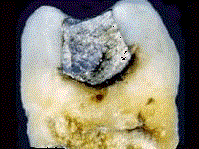

问题 继发龋的致病因素是 ( )

选项 A.充填物边缘破裂 B.窝洞周围牙体组织破裂 C.充填物与牙体组织不密合 D.龋坏组织未去除干净 E.以上都是

答案 E